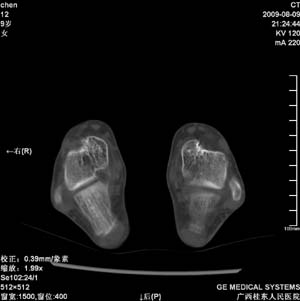

标题: PED2867:右侧内踝肿胀,骨质改变,请各位老师会诊 [打印本页]

标题: PED2867:右侧内踝肿胀,骨质改变,请各位老师会诊

九岁小朋友,近期左侧内踝疼痛,局部肿胀,平时无特殊,近期经常溜干冰

对不起,是右侧内踝肿胀

双踝关节骨质及发育未见异常。

左侧内踝密度增高,请结合临床!